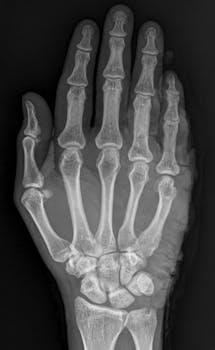

Carpal tunnel syndrome is a condition that affects the hand and wrist due to pressure on the median nerve. This pressure can result from repetitive hand movements, wrist position, or various health conditions. Medical devices play a critical role in providing relief by maintaining proper wrist alignment, reducing inflammation, and improving nerve function.